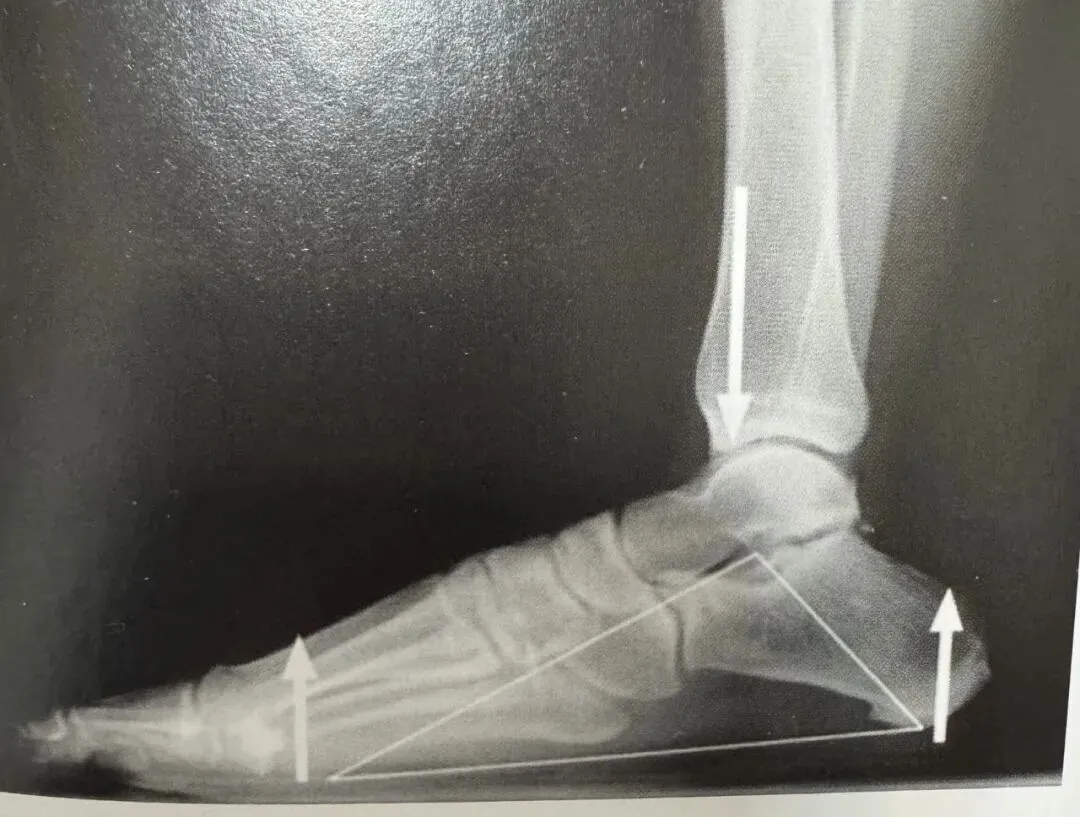

大部分足跟痛患者年龄为40~70岁、男性、爱活动、正常足弓单侧发病。肥胖是易患因素之一;当患者体重过重时,症状更难控制。患者主诉为跟下疼痛,晨起或坐片刻后加重,行走几步后疼痛减轻。白天患者相对较舒适,到傍晚疼痛逐渐加重,不负重后可缓解。最常见的体征是跟骨结节内下侧的局限性压痛。如将患侧与对侧足跟相比,可发现有轻微肿胀及发红,症状持续时间从数周、数月到数年不等。约50%患者X线片示有跟骨骨质增生,但此现象的确切意义尚不肯定。虽然本病诊断主要依靠临床,通过排除其他病变确立诊断,但是骨扫描可能有些帮助。当患者的后跟痛是根据临床印象做出的一个不明确的诊断,且经过常规治疗很长一段时间仍无效,或者需要排除应力骨折,此时骨扫描会有帮助。